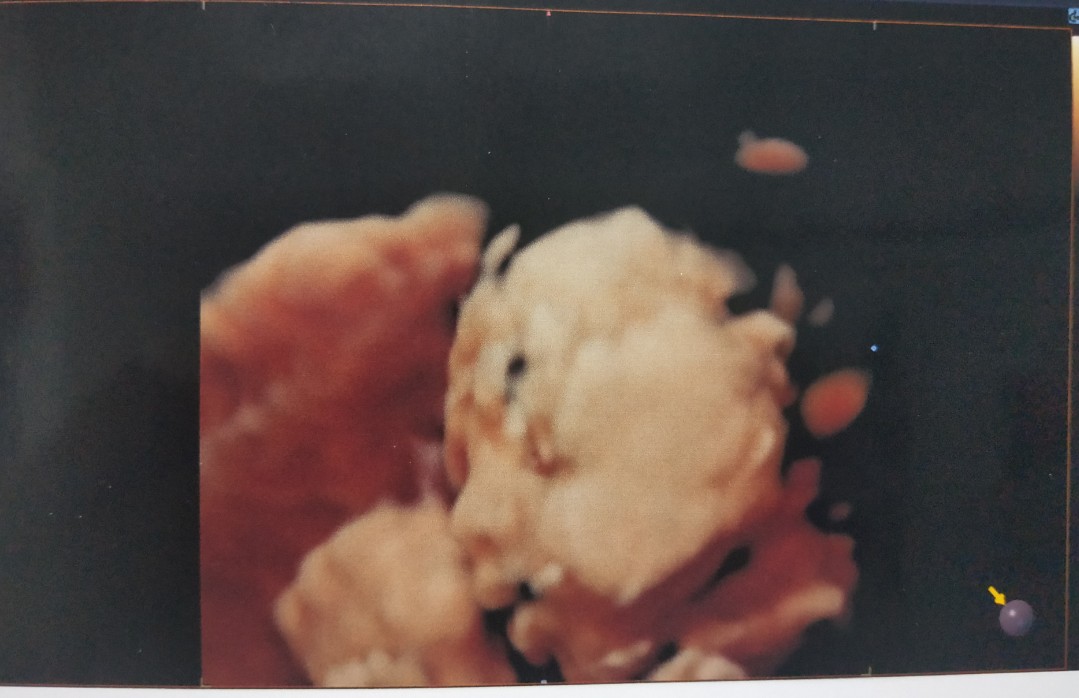

28 week ค่ะ

ลูกสาวค่ะ